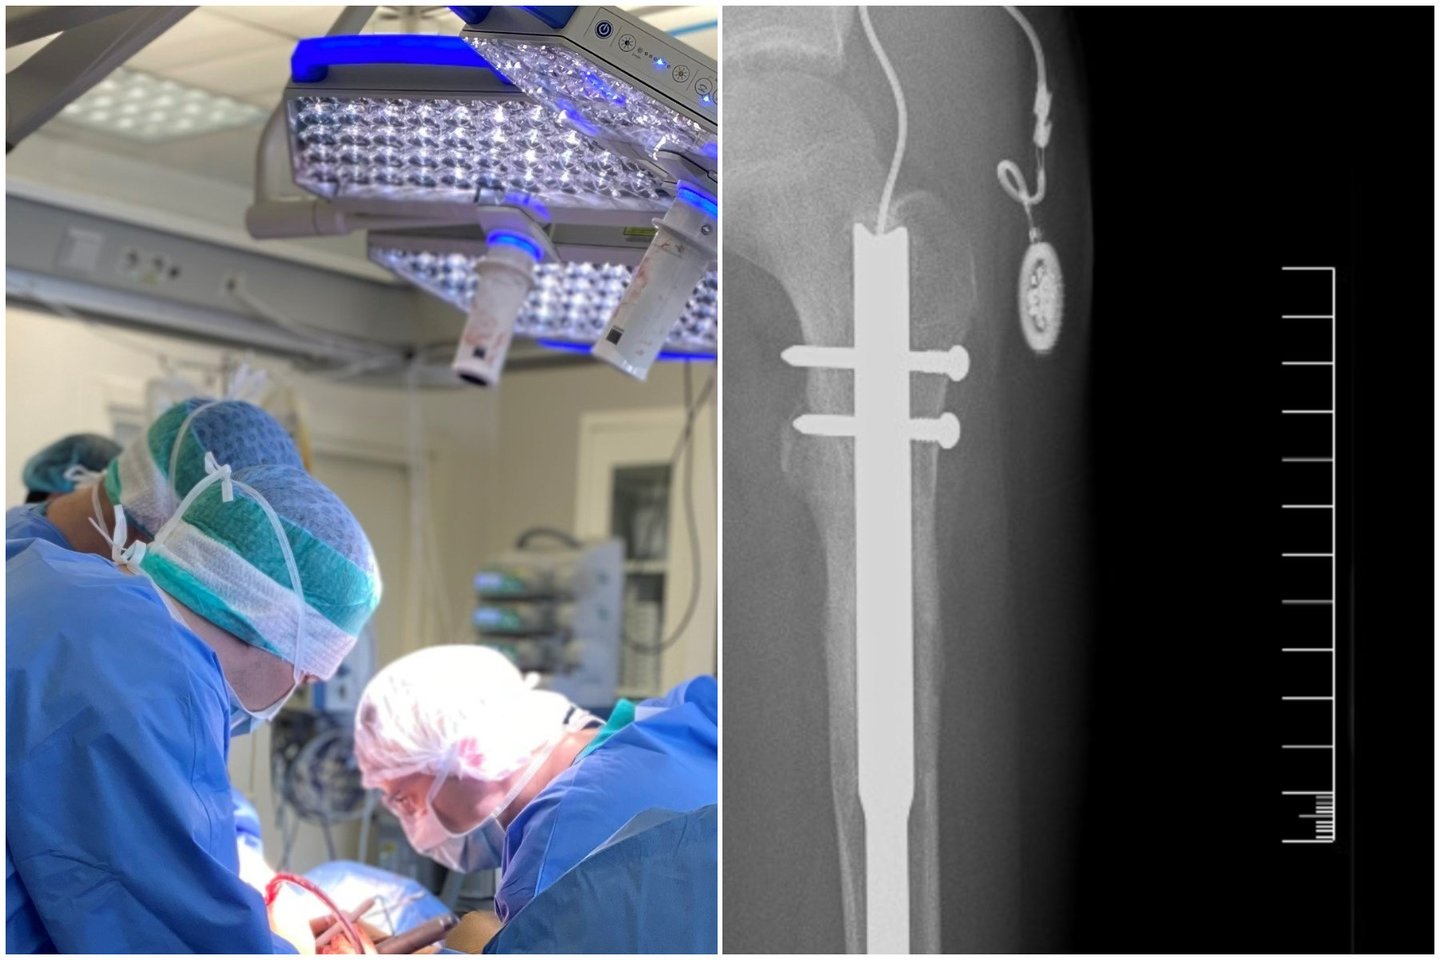

Santaros klinikų nuotr.

Pirmiausia specialiais grąžtais buvo išvalytas šlaunikaulio kanalas, kad būtų galima į jį įstatyti reikiamo dydžio implantą: „Vinys yra įvairių dydžių, todėl kanalą reikia paruošti labai tiksliai pagal pasirinktą implantą“, – aiškina gydytojas.

Tuomet atlikta osteotomija – kaulas perpjautas per suplanuotą vietą, suformuojant dirbtinį lūžį. Į vidų įdėta ir fiksuota magnetinė vinis. Po oda implantuojamas specialus daviklis, per kurį siunčiami impulsai kaului ilginti.

„Vienas iš didesnių techninių iššūkių buvo būtent daviklis, nes po oda, ypač esant patinimui, jį kartais sudėtinga užčiuopti. Po operacijos žymėjome ant odos jo vietą markeriu, vėliau pacientas pats tiksliai žinojo, kur jis yra, ir galėjo procedūrą atlikti savarankiškai“, – dalinasi patirtimi gydytojas.